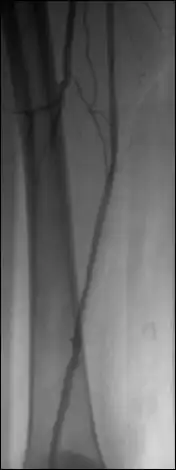

Display the image sequence in the 2D Viewer and activate the subtraction module (use Format | Customize Toolbar... if this module is not displayed in the toolbar of the 2D Viewer).

The image number used for the mask image is displayed – the first image of the sequence is the default mask. Browse through the sequence and adjust the WL/WW as needed. Click on the ‘current’ button to select another mask image.